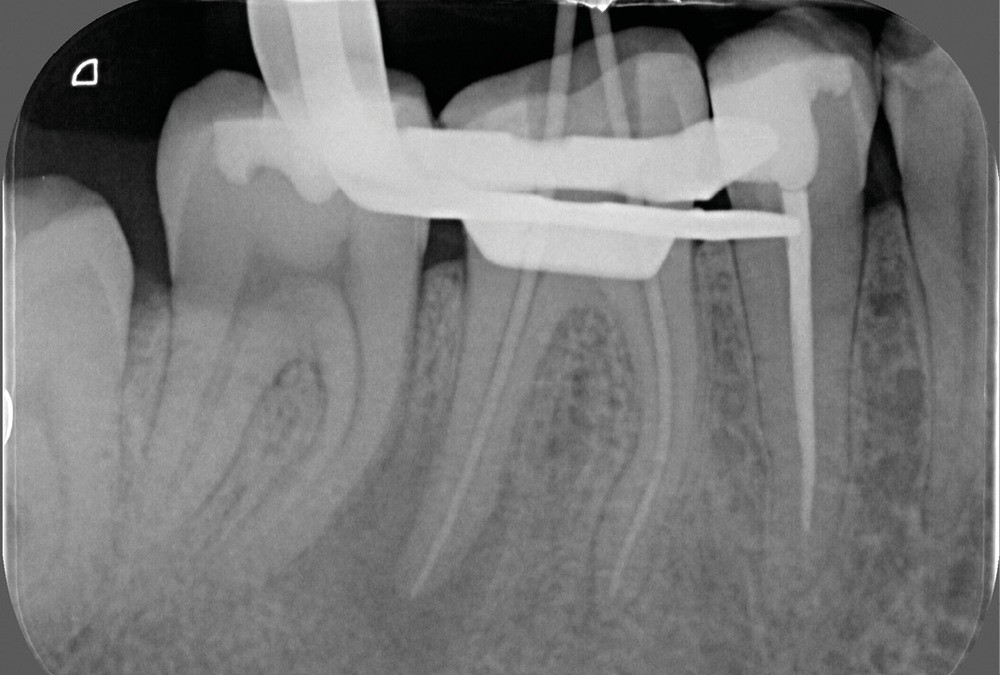

La préparation mécanique est principalement réalisée à l’aide d’instruments NiTi utilisés en rotation continue ou en réciprocité selon une approche corono-apicale. La mise en forme est ainsi plus rapide et respecte mieux le trajet canalaire initial qu’avec une instrumentation manuelle. Le diamètre apical et la conicité de la préparation canalaire font toujours débat. Ils dépendent de l’anatomie initiale et doivent permettre une irrigation efficace sans fragiliser la dent. Ainsi, un diamètre apical de 30 et une conicité de 6 % sont souvent proposés comme objectif minimal à atteindre [3] (fig. 1).